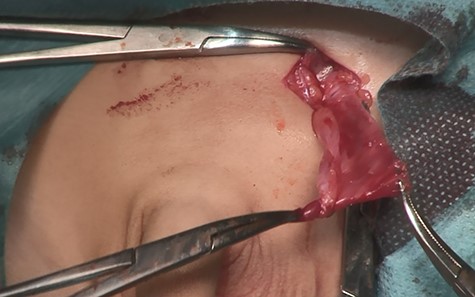

A14-month-old boy was admitted to our hospital to undergo inguinal orchidopexy. At the age of 1 month, the left testis was palpable between the inguinal canal and the scrotum. When he was 6 months old, ultrasonography showed the left testis inside the inguinal canal (Fig. 1). At the age of 13 months, the patient was seen in the outpatient clinic for preoperative examination in preparation for inguinal orchidopexy; the left testis was not palpable at that time. At the age of 14 months, we began surgery with a preoperative diagnosis of an undescended testis. When the inguinal canal was opened, only a patent processus vaginalis was visible (Fig. 2). After incision of the membrane, we were able to retrieve the testis from the abdominal cavity (Fig. 3a). The patent processus vaginalis was closed, a dartos pouch was created and the testis was guided into the pouch and fixed to its wall (Fig. 3b).

Intraoperative photography (14 months of age). After opening the inguinal canal, only a patent processus vaginalis is visible.

Intraoperative photography (14 months of age). (a) The testis is retrieved from the abdominal cavity. (b) After the patent processus vaginalis is closed, the testis is guided into a dartos pouch and fixed to the pouch wall.